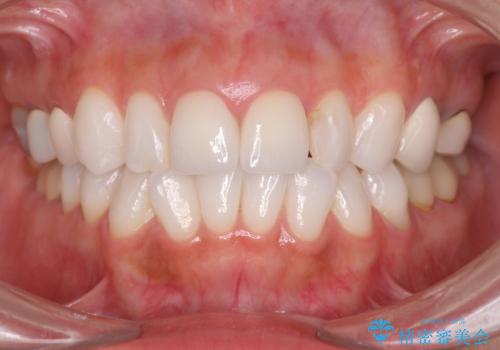

ラミネートベニヤの破折 ジルコニアクラウンによるやり替え

- 26.4万円(ジルコニアクラウン×2・仮歯×2)費用は治療当時の料金となります

歯の大きさの不揃いが改善されただけでなく、色調もよくなり審美性をしっかりと改善することができました。